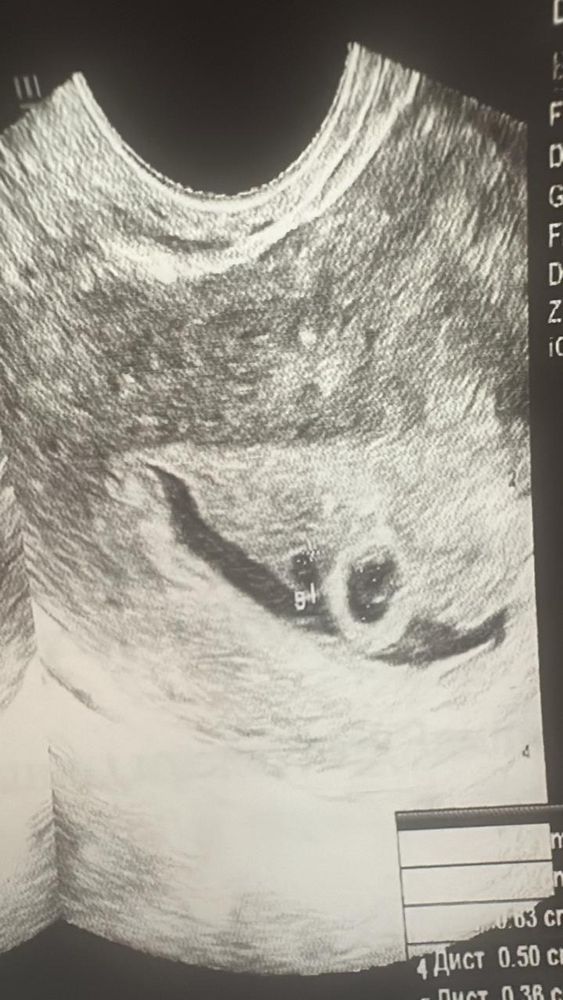

Беременная. Последние месячные 05.12.2024 года. 16.01.2025 года сходила на первый УЗИ. Срок ставили 3-4 недели. Двойня под вопросом. И гематома размером 18*3 мм. Через неделю 23.01.2025 года сделали контрольный УЗИ. Срок 4-5 недели. Двойню подтвердили. Но один по развитию отстает. А гематома дольше два раза.

сказали прийти еще на одну контрольную УЗИ через неделю. Еще в этот же день сдала анализ на хгч. Результат 2225 мМЕ/мл через 48 часов сдала еще один его результат 2449 мМЕ/мл. Дорогие доктора гинекологи скажите пожалуйста какого шанс что беременность сохранится и обе плода останутся??? С детства мечтала о двойне 😌

Прикрепила снимок двух УЗИ

1) 16.01.2025

2) 23.01.2025